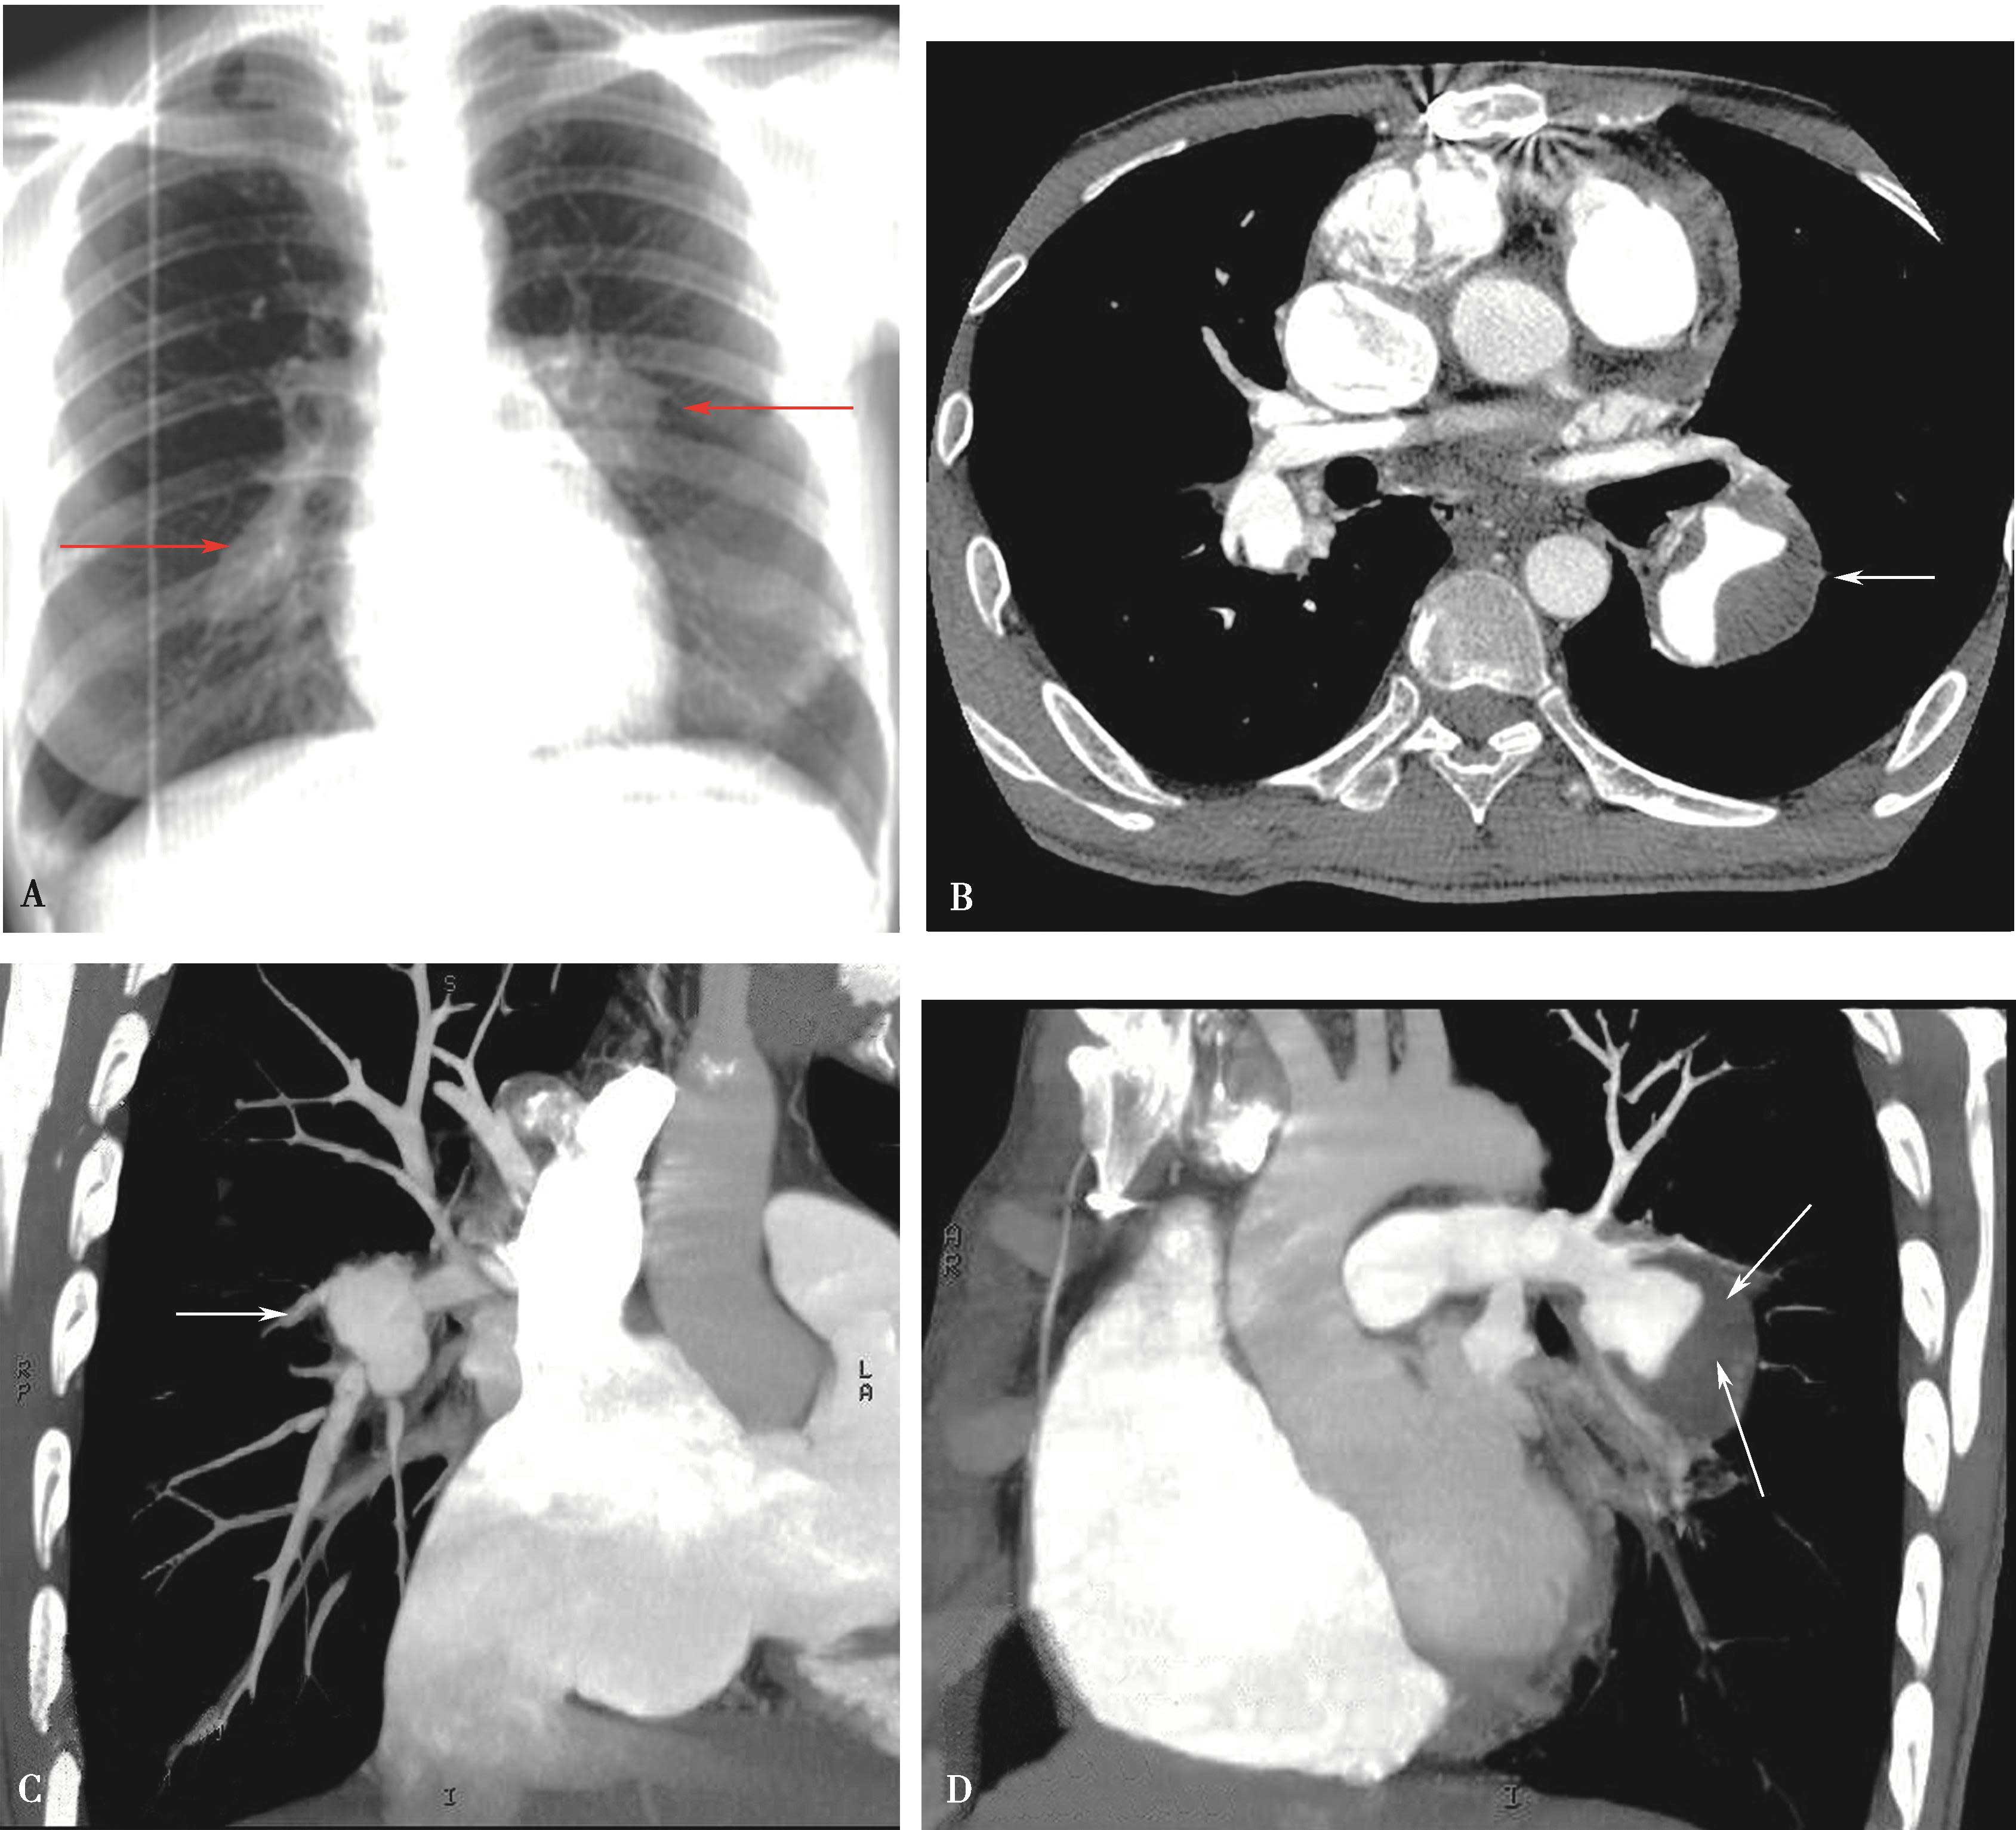

图8-5-5 男,28岁,反复口腔及生殖器溃疡5年,白塞病,肺动脉瘤

A.胸部X线片,示左右肺动脉瘤(↑);B.横断图像,左、右下肺动脉动脉瘤形成,附壁血栓形成(↑);C.多层重组(冠状位)示右下肺动脉动脉瘤合并附壁血栓(↑);D.多层重组(左前斜位)示左下肺动脉瘤合并附壁血栓形成(↑)。CT诊断:左右肺动脉瘤,附壁血栓形成,病变性质白塞病